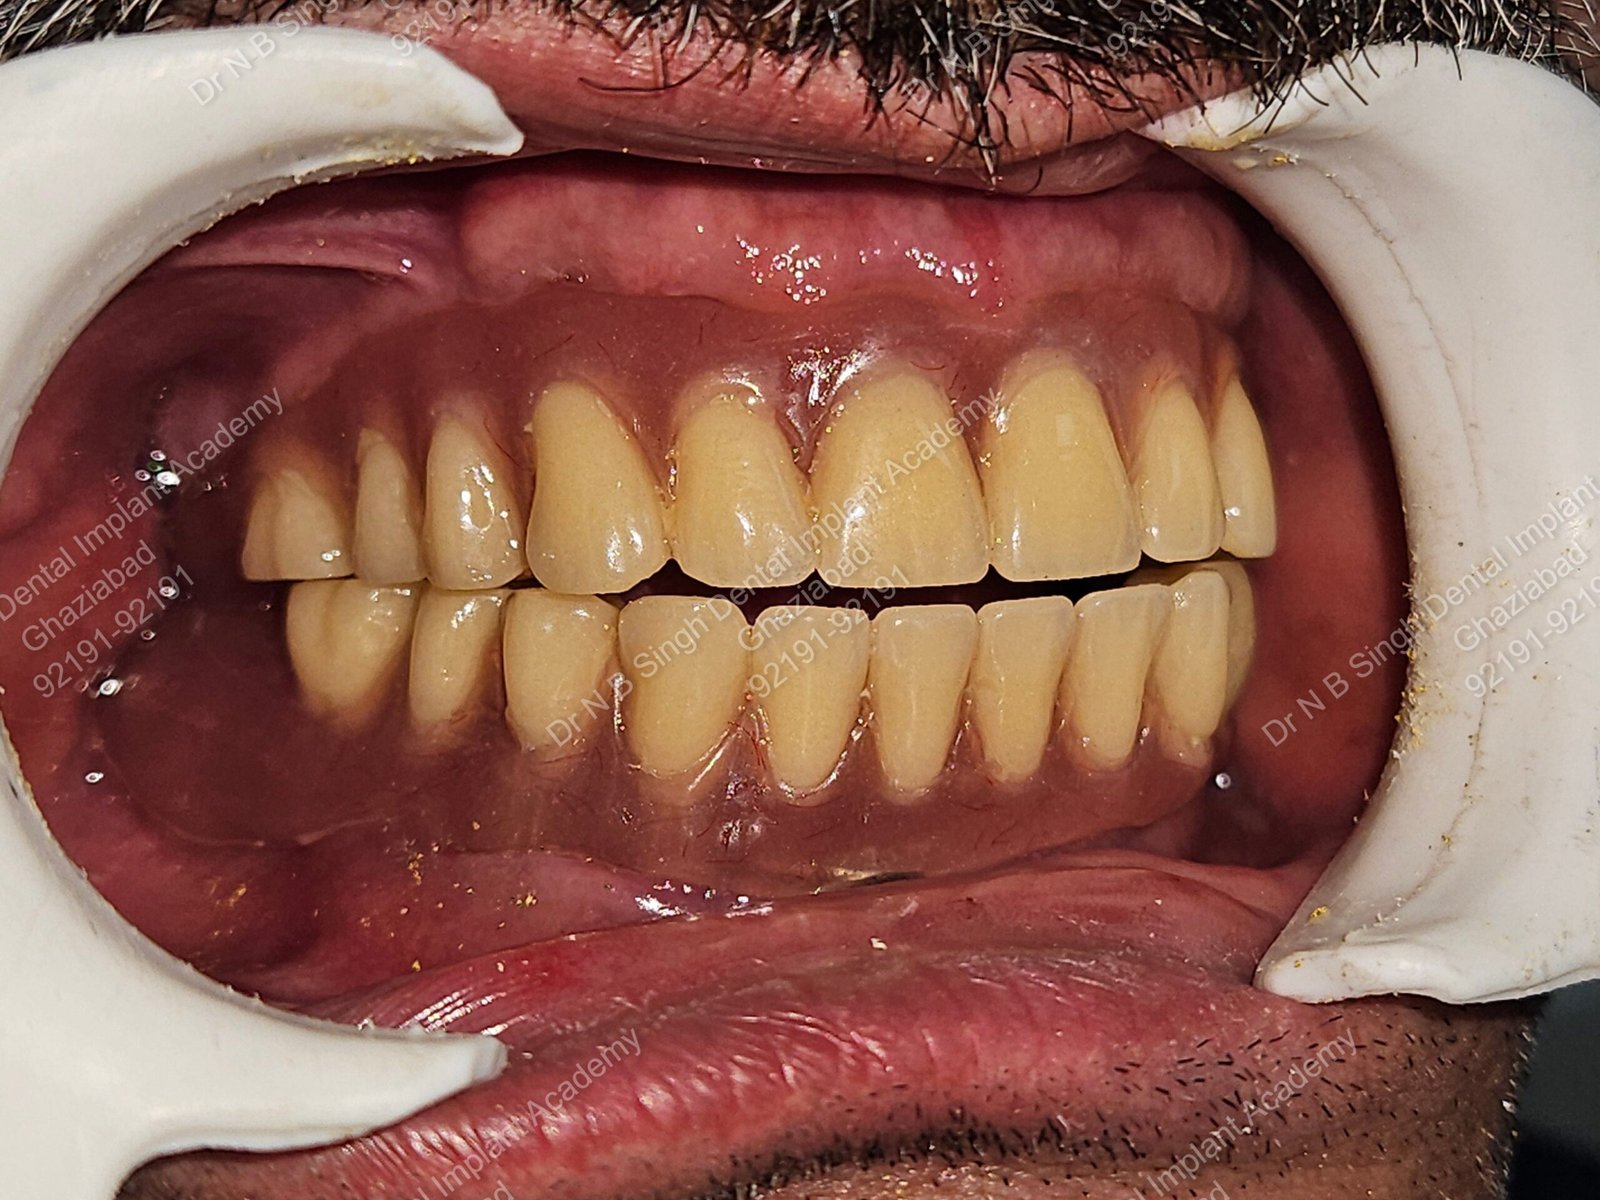

1006 Basal implant full mouth-DEEPAK

1006 -29

1006 -28